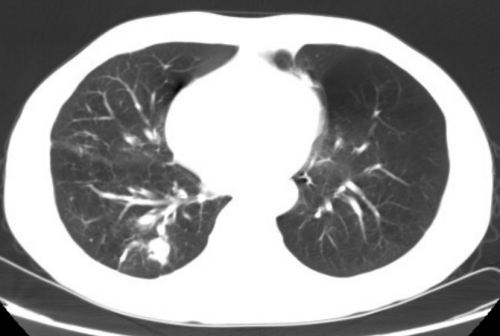

体检发现右下肺结节

据了解,王先生长期吸烟,有多年的慢性支气管炎、肺气肿,11月24日因CT体检发现右下肺结节,于12月1住进普胸外科、心脏大血管外科。普胸外科、心脏大血管外科副主任医师罗化接诊了他。经过PET-CT检查,王先生患肺癌可能大,无远处及淋巴结转移,需手术治疗。但考虑王先生年龄大,又长期吸烟,有慢性阻塞性肺部疾病,肺功能差,难以耐受肺全麻胸腔镜手术。科室副主任、主任医师杨继承查看患者后立即组织团队研究讨论,决定采取肺部微波消融治疗。为了缓解王先生的紧张情绪,杨继承告知王先生:“目前针对肺结节、肺癌有很多方法,除了常规胸腔镜手术外,还可以进行局部消融术,就是在CT引导下经皮肺插一根针到肺部结节中,几分钟结节就消失,不需要全麻,恢复快,创伤小”。王先生听后打消了疑虑,欣然接受。